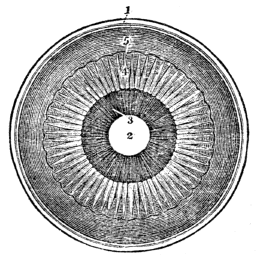

| 44. | Anatomy of the Organs of Vision, | 394 |

| 45. | Physiology of the Organs of Vision, | 404 |